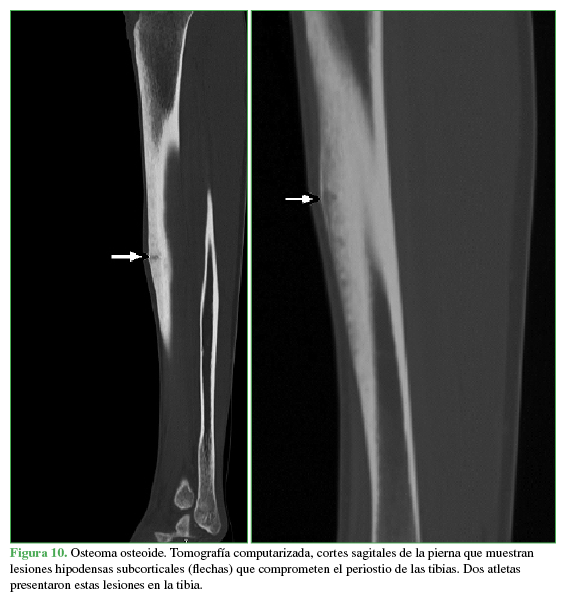

Las distintas patologías informadas se muestran en la Tabla 6 y las Figuras 6,7,8,9,10,11 y 12.

Tomografía axial computarizada, cortes sagitales de la pierna que muestran lesiones hipodensas subcorticales (flechas) que comprometen el periostio de las tibias. Dos atletas presentaron estas lesiones en la tibia